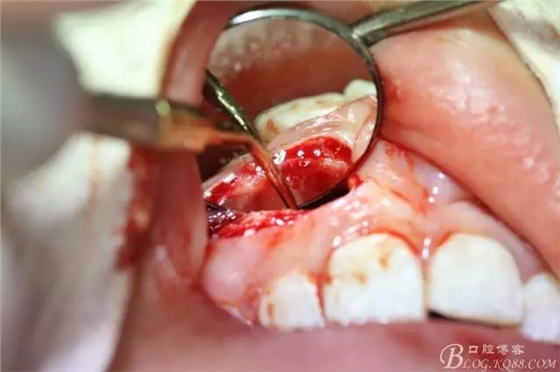

病例資料: 患者、柴xx、女、16歲。??茩z查及病歷如下圖: 患者同意我院正畸科建議,遂轉(zhuǎn)診倒外科。術(shù)前簽知情同意書。 治療過程: 圖1.術(shù)前的CBCT檢查:13阻生,疑為含牙囊腫。縱剖面顯示12牙根吸收至根尖1/3。 圖2.局部麻醉下 。行唇側(cè)弧形切口,12松動不到1°。 圖3.翻瓣、暴露骨面。 圖4.去骨、 暴露13牙冠 圖5.去骨、逐漸顯露13。 圖7.拔除13. 圖8.摘除囊壁 圖9.必須完整剝離囊壁。 圖10.摘除囊壁后形成的骨腔 圖11.超聲骨刀12根尖倒預(yù)備 圖13. 消毒棉球骨腔內(nèi)隔濕血液,紙尖干燥倒預(yù)備好的根管 圖14. 紙尖無血即可 圖15。MTA倒充填 圖16.骨腔填塞膠原蛋白海綿 圖17.拔除的13及摘除的囊壁 圖18.縫合 圖19.術(shù)后x線根尖片影像:MTA封閉根尖